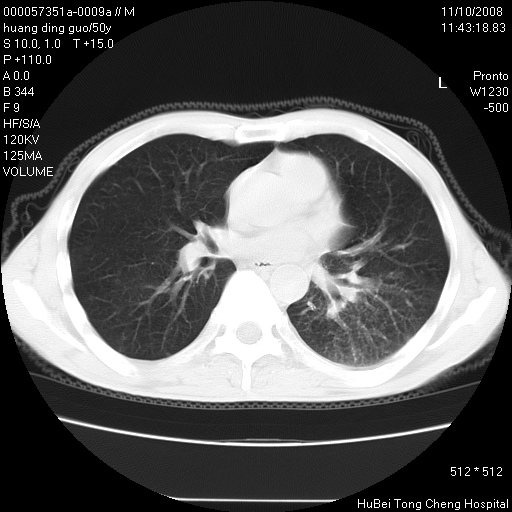

患者 男,50岁。左侧腰背部疼痛3月余,伴消瘦。平素健康,无传染病史。

胸部ct轴位平扫(层厚10mm,螺距1.5,重建间隔10mm),图像如下:

左肺下叶背段有一厚壁空洞,外壁呈锯齿状伴毛刺改变。空洞相邻胸膜有牵拉改变。左肺下叶血管支气管束不规则增粗,小叶间隔增厚。胸椎骨质破坏。考虑左肺下叶周围型肺癌伴左肺下叶癌性淋巴管炎、胸椎转移。

左肺下叶背段有一厚壁空洞,外壁呈锯齿状伴毛刺改变。空洞相邻胸膜有牵拉改变。左肺下叶血管支气管束不规则增粗,小叶间隔增厚。胸椎骨质破坏。考虑左肺下叶周围型肺癌伴阻塞性肺炎、胸椎转移。其他待排

左肺下叶背段有一厚壁空洞,内壁不规则,外壁呈锯齿状伴毛刺改变。空洞相邻胸膜有牵拉改变。周围呈絮状炎性改变,左肺下叶血管支气管束不规则增粗,小叶间隔增厚。胸椎骨质破坏。考虑左肺下叶周围型肺癌伴左肺下叶阻塞性肺炎、胸椎转移。